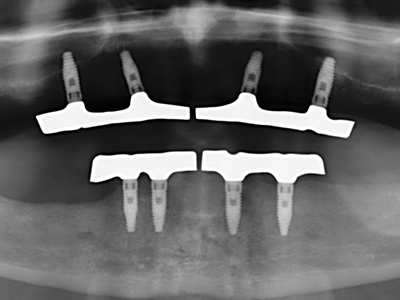

Bilder klinischer Anwendungsfälle